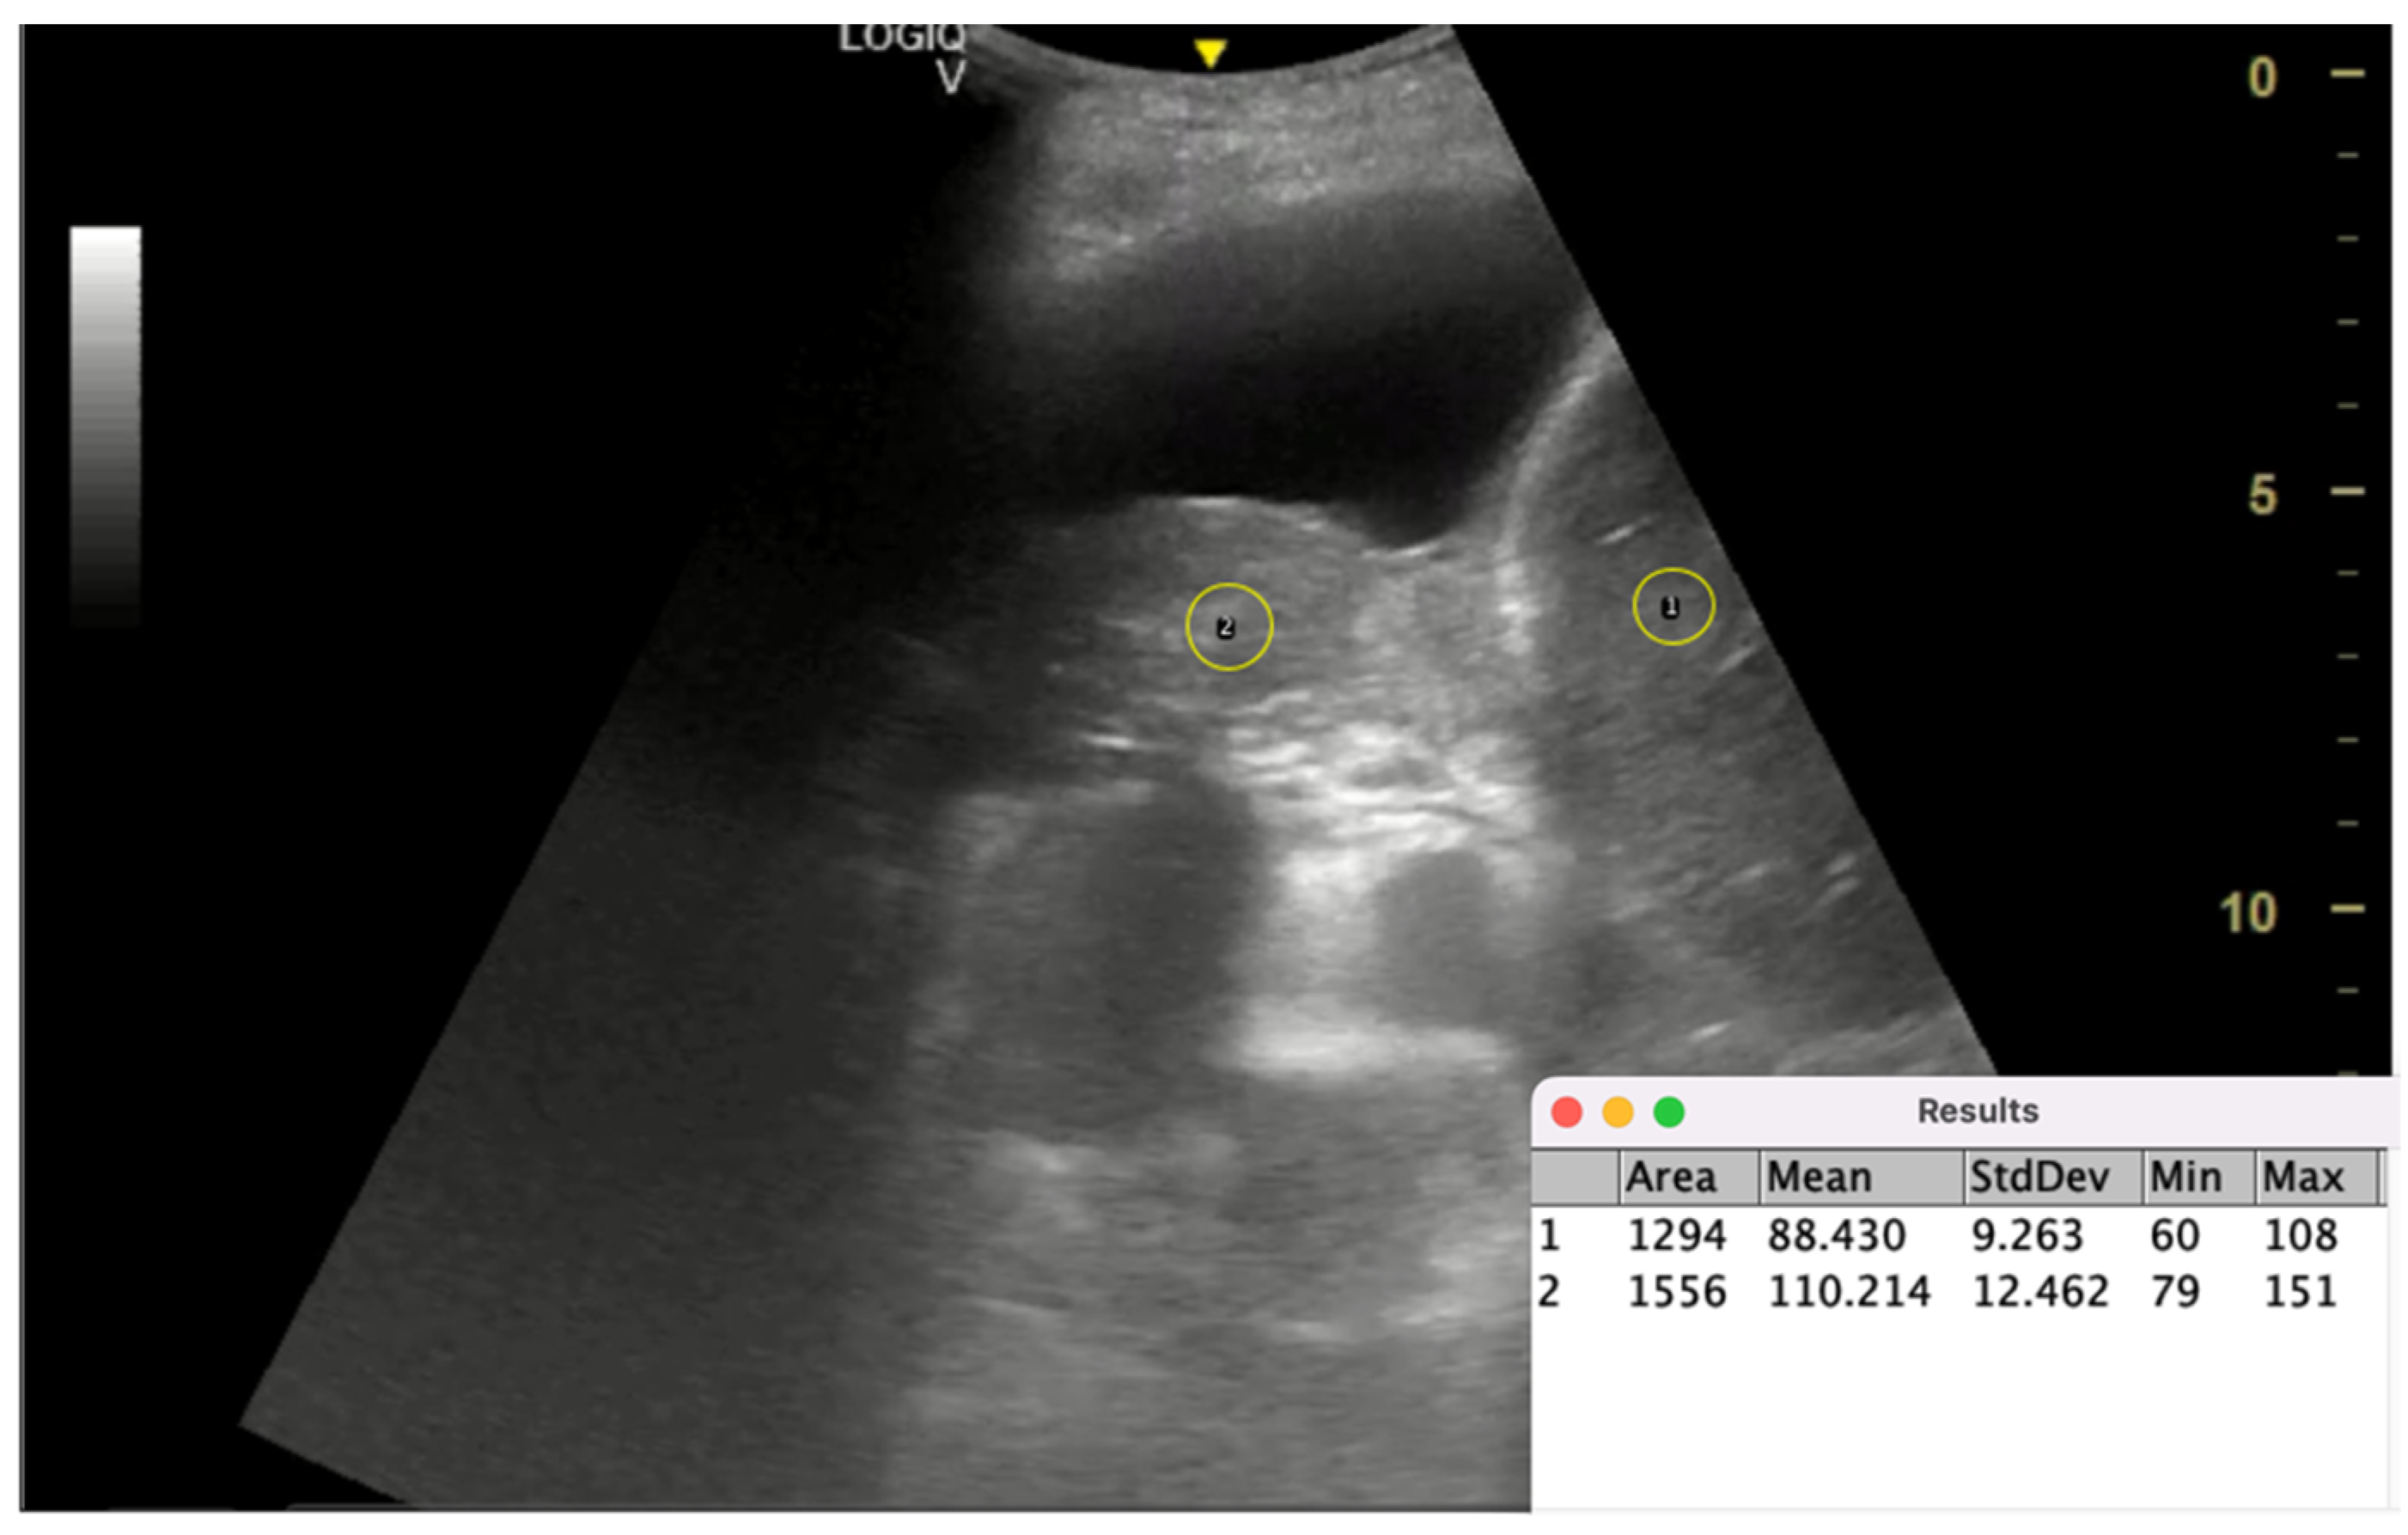

5.2.3. Lung/Liver Echogenicity (LLE) Ratio

- Schroeder, A.B.; Dobson, E.T.A.; Rueden, C.T.; Tomancak, P.; Jug, F.; Eliceiri, K.W. The ImageJ Ecosystem: Open-Source Software for Image Visualization, Processing, and Analysis. Protein Sci. 2021, 30, 234–249. [Google Scholar] [CrossRef]

- Harris-Love, M.O.; Seamon, B.A.; Teixeira, C.; Ismail, C. Ultrasound Estimates of Muscle Quality in Older Adults: Reliability and Comparison of Photoshop and ImageJ for the Grayscale Analysis of Muscle Echogenicity. PeerJ 2016, 4, e1721. [Google Scholar] [CrossRef]

- Spinnato, S.; De Biase, A.; Bilardo, C.M.; Elvan-Taşpınar, A. Fetal Echogenic Bowel: What Is Real Echogenicity? A Quantitative Method Based on Histogram Analysis of the Grayscale. Fetal Diagn. Ther. 2024, 51, 145–153. [Google Scholar] [CrossRef]

- Di Matteo, A.; Moscioni, E.; Lommano, M.G.; Cipolletta, E.; Smerilli, G.; Farah, S.; Airoldi, C.; Aydin, S.Z.; Becciolini, A.; Bonfiglioli, K.; et al. Reliability Assessment of Ultrasound Muscle Echogenicity in Patients with Rheumatic Diseases: Results of a Multicenter International Web-Based Study. Front. Med. 2023, 9, 1090468. [Google Scholar] [CrossRef]

| Hassan et al. [21] | 2021 | Validate TUS predictors of NEL | Prospective cohort | 29 patients with pleural effusion | M-mode, lung/liver echogenicity (LLE) ratio | M-mode alone was a poor predictor (AUC = 0.48), LLE ratio was better (AUC = 0.77) | LLE may serve as a better predictor for NEL than M-mode alone | Small sample size, single-center study |

| lung/liver echogenicity (LLE) ratio | Compares grayscale pixel density of lung and liver via ImageJ software | Predicting lung re-expansion after pleural drainage | LLE > 1.6 predicts NEL with AUC = 0.77 | Simple, reproducible, quantitative | Limited validation, small study population, dependent on image quality | Lacks direct validation against; potential role as adjunct to manometry | Requires software (ImageJ) and proper grayscale calibration, moderately operator-dependent | Larger, multicenter studies, AI-based echogenicity analysis, validation in different effusion types |